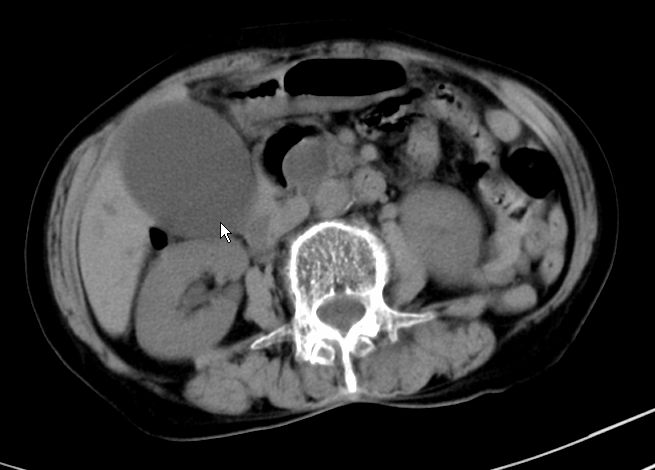

以下是引用zjzjr在2008-12-16 12:49:00的发言:[br]肝内外胆管全程扩张,胆囊明显增大,未见占位征像.建议mrcp.

以下是引用jiangjing在2008-12-16 13:19:00的发言:[br]肝内外胆管全程扩张,胆囊明显增大,扩张胆总管下段径较中上段小,未见胰管扩张,提示胆总管远端梗阻伴感染.建议增强及mrcp 检查

以下是引用朱亮在2008-12-16 12:54:00的发言:[br]胆总管远端应薄层扫描 胆总管逐渐变细 考虑胆系慢性炎症